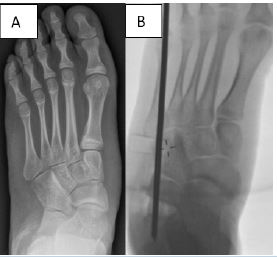

Radiographic evaluation of deformity correction included measurement of the calcaneal pitch angle (normal range, 18°–32°), Meary’s angle (normal range, –4° to +4°), and talonavicular coverage angle (normal, < 7°) [10,11]. Coalition was confirmed radiographically with CT (Figure 1). Hindfoot valgus was measured on coronal CT reformats, with a valgus angle greater than 16° considered the threshold beyond which isolated RC was not recommended [6,12,13].

Figure 1: CT scan conformation of talo-calcaneal coalition with hindfoot valgus.